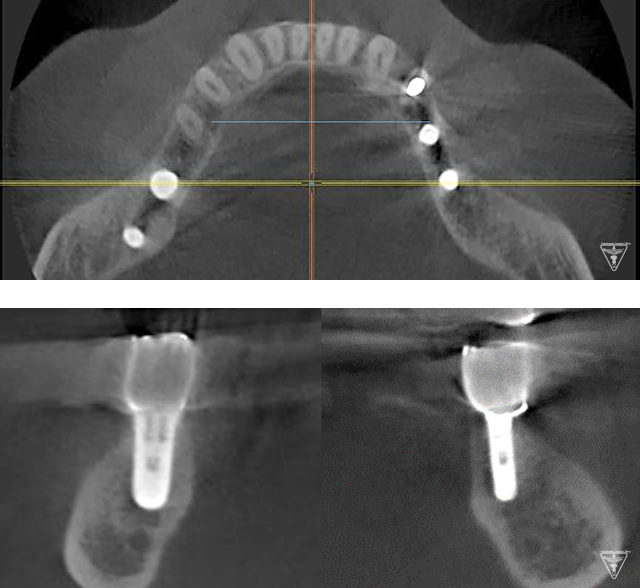

CTによるインプラント埋入位置の評価

多血小板血漿を遠心分離機により抽出し、完全自己血液由来によりアレルギーや感染のリスクの軽減、傷の治り、骨や歯肉の再生が促進され治療期間の短縮が実践できた。